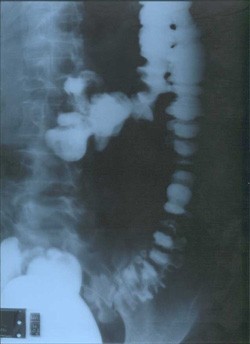

La diverticolosi del colon è una patologia comune che interessa circa la metà della popolazione tra i 60 e gli 80 anni, ma non è infrequente anche nei più giovani. È caratterizzata dalla presenza di estroflessioni nel colon, in particolare nei suoi tratti di sinistra ma può interessare tutto il grosso intestino. Si definisce diverticolosi la semplice presenza dei diverticoli senza alcuna sintomatologia mentre è detta diverticolite ogni situazione patologica che comporti un’infiammazione dei diverticoli con possibilità di complicanze.

La presenza di diverticoli nell'intestino spesso non dà alcun sintomo particolare e la maggior parte delle persone se ne accorge solo in seguito ad esami (colonscopia o clisma opaco) condotti per altre ragioni a o scopo preventivo. I diverticoli sembrano essere causati dal cedimento delle pareti del colon, dovuto a un aumento della pressione sulle stesse dovuto ad un colon contenente una scarsa quantità di residuo fecale a causa di una dieta povera di scorie. In questo caso la secondaria alterazione della peristalsi può provocare spasmo con dolori addominali e difficoltà di evacuazione. In questi casi la diagnosi differenziale con la cosiddetta sindrome del colon irritabile può essere difficile per il concomitare dei due problemi con sintomi spesso sovrapponibili.